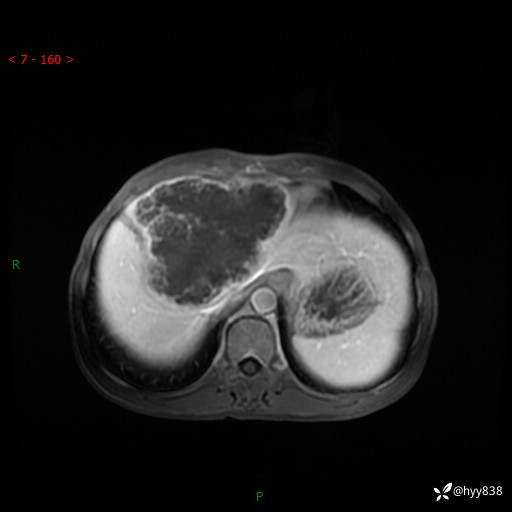

【患者信息】:58岁/男

【主诉】:发现肝占位2天

【现病史及既往史】:患者2天前于当地市第五医院查上腹部磁共振提示:肝脏S4段占位性病变,肝ca可能,胆囊结石,腹膜后多发肿大淋巴结,无剑突下及右上腹疼痛不适,无明显反酸、嗳气,无畏寒、头晕、头痛,无尿频、尿急、尿痛等不适,今为求进一步治疗特来我院就诊,门诊以“肝占位”收住我科。 患者病程中精神、睡眠、饮食尚可,大小便正常、体力体重无明显变化

【检查】:肝脏MRI】平扫+增强